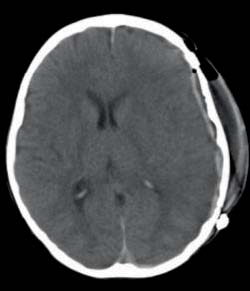

A craniotomia descompressiva ocorreu cerca de 45 minutos após a realização de TC-CE e da reversão da anticoagulação (56 horas após o início da sintomatologia). Realizada drenagem de todo o hematoma, sem visualização do ponto sangrante, com consequente expansão cerebral, constatando-se edema cerebral generalizado. No pós-operatório manteve as medidas anti-edema cerebral e ventilação mecânica durante quatro dias. Clinicamente, houve regressão da anisocoria e melhoria progressiva, apesar de às 48h de pós-operatório ter havido diminuição do nível de consciência. Fez TC-CE (Figura 2) que não apresentava alterações. Às 32h de pós-operatório, reiniciou anticoagulação com enoxaparina subcutânea (1 mg/kg/dose).

FIGURA 2 - Secção de TC-CE sobreponível à anterior, realizada 24 horas após a cirurgia, mostrando sequelas da intervenção e resolução do hematoma